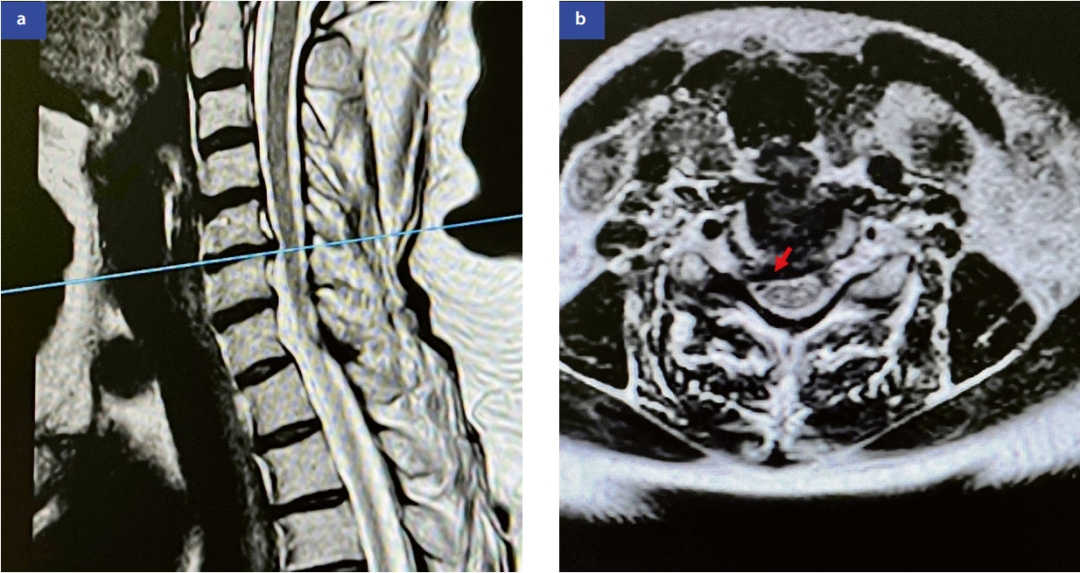

MRIMRI(图1)在软组织分辨率上优于CT,可清晰显示神经、关节和脊髓。诊断神经压迫的敏感性达93%。

图1:颈椎磁共振成像矢状位(a)和轴位(b)显示C5/C6节段右侧中外侧椎间盘突出(红色箭头标示)